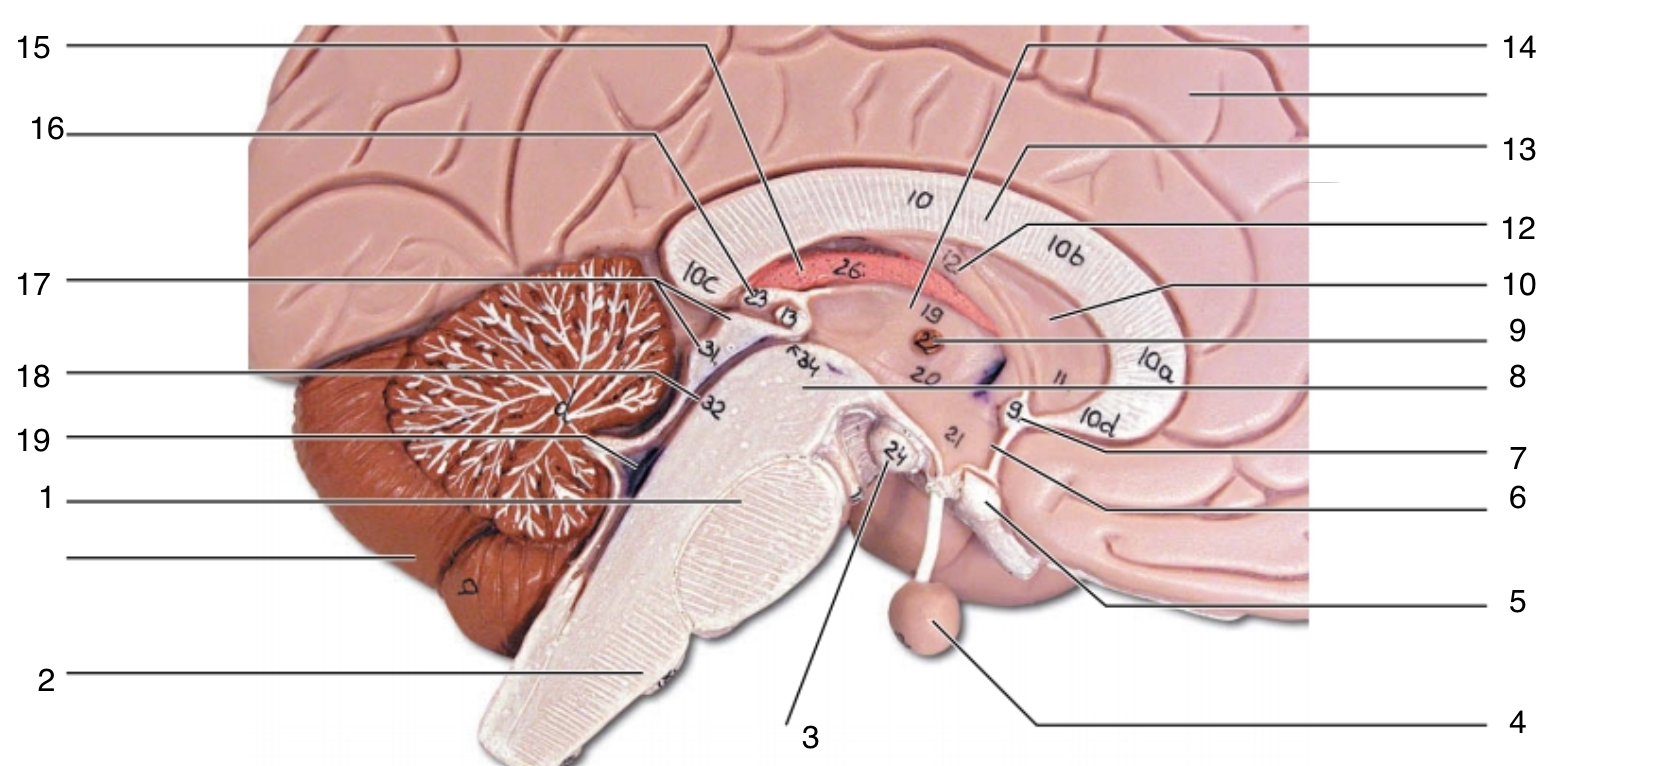

Brain Stem

1

pons

1

2

medulla oblongata

2

3

mammillary body

3

4

pituitary gland

4

5

optic chiasma

5

6

hypothalamus

6

7

anterior commissure

7

8

midbrain

8

9

interthalamic adhesion

9

10

septum pellucidum

10